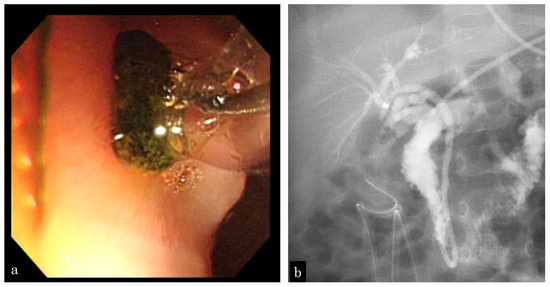

3.1.1. Patient 1

3.1.2. Patient 2